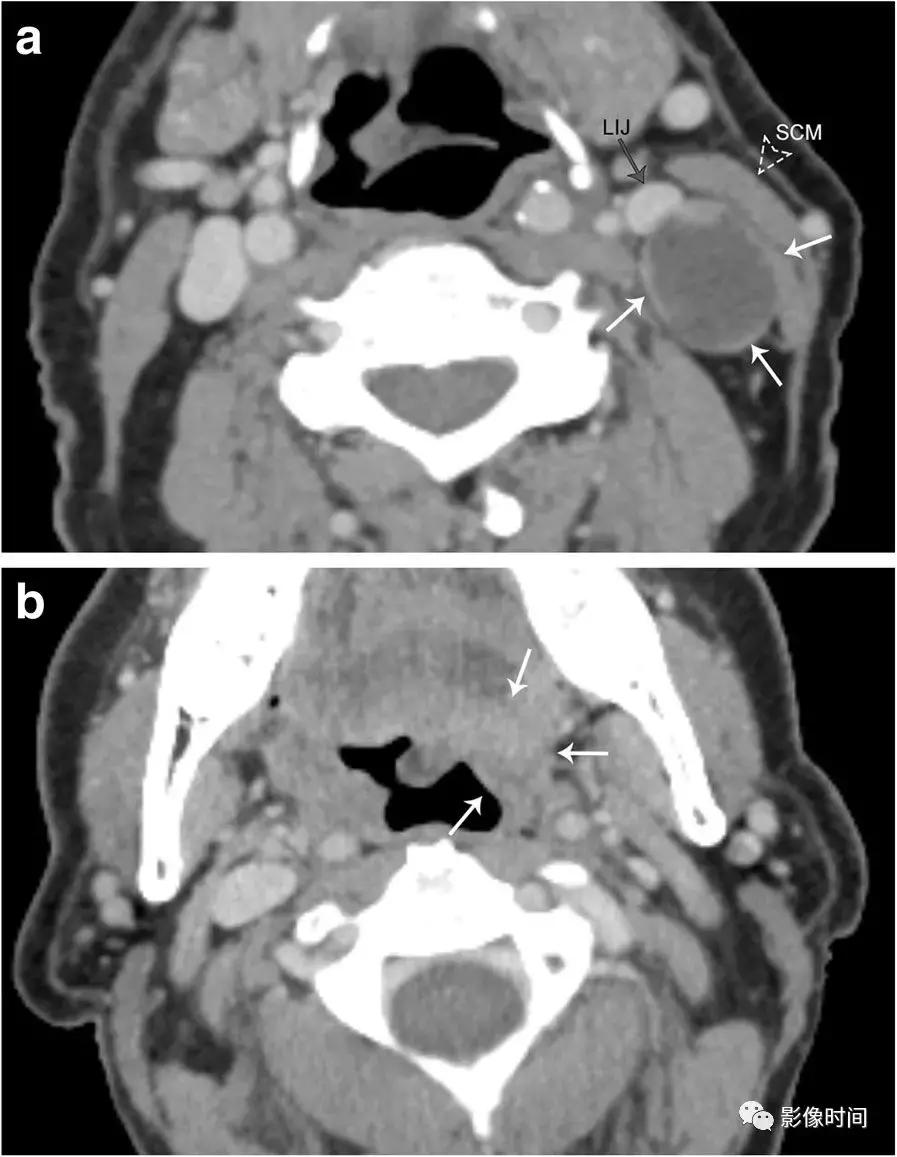

a. 患者表现为明显的左颈部肿块。增强 CT 显示左侧颈动脉间隙淋巴结边界清晰、稍低密度,伴壁结节 (白色箭头),导致左颈内静脉 (LIJ) 前内移位和胸锁乳突肌 (SCM) 向外移位。b. 同一患者舌根水平增强 CT 图像显示左舌底部 (箭头) 有一个不明确的肿块,活组织检查为鳞状细胞癌。